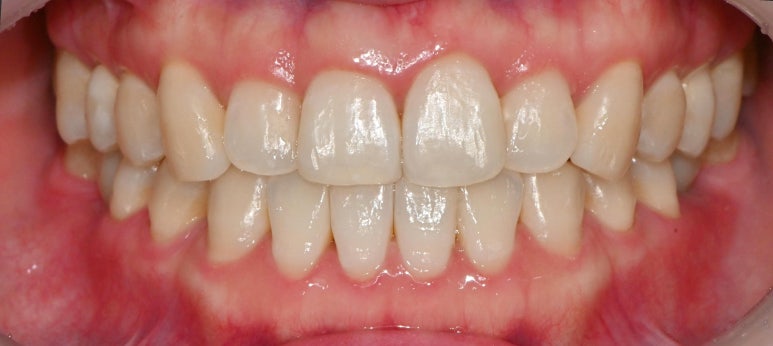

서울대입구역 교정 치과 에서

모든 진료가 끝나고 난 뒤

구내 모습을 보면

본래의 색과 비슷한 크라운을 올려드렸으며

저작 기능을 잘 수행할 수 있도록

적절한 사이즈의 보철을 제작하여

수복해 드렸습니다.

윗니도 마찬가지로

총생을 개선함과 동시에

본래의 자리로 돌아가지 않도록

안쪽에 유지 장치를 부착해두었습니다.